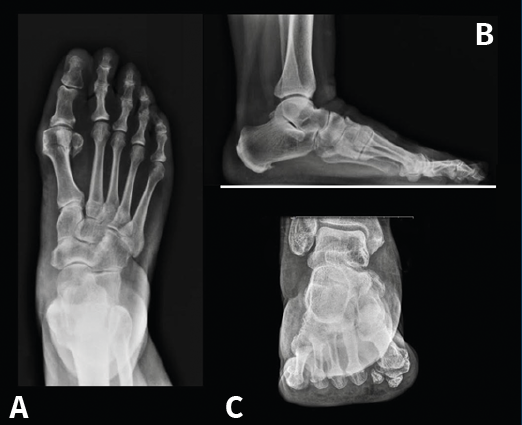

Figura 13. Caso del Dr. Martín Ferreyra. Imágenes radiológicas preoperatorias. A: dorsoplantar; B: perfil; C: axial de los sesamoideos.

Es por ello que en la actualidad autores como E. y P. Wagner(68) realizan una osteotomía tridimensional, no solo en el plano transversal, a la que denominan PROMO. En el caso de la artrodesis cuneometatarsiana sucede lo mismo y una de las tendencias actuales es realizar un Lapidus modificado tridimensional(69,70), como puede verse en el caso de M. Ferreyra (Figuras 13 a 15), en el que la estabilización con 2 placas permite una carga precoz.